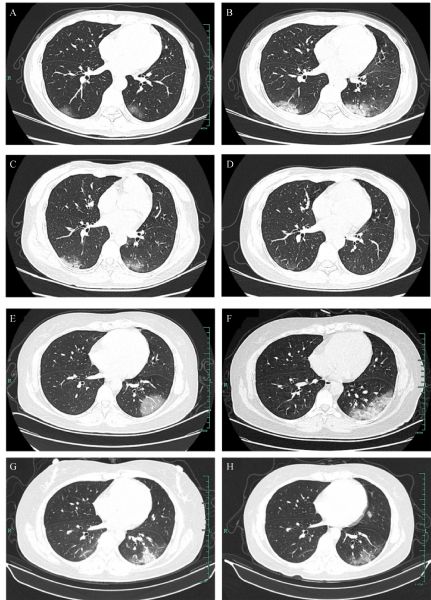

Yu Wang, Lan Li, Yuanjiang Pan, Yu He, Zuhua Chen, Yunhao Xun, Yuhan Xu, Yilei Guo, Jiehong Yang, Jianchun Guo, Haitong Wan

Cardio-cerebrovascular disease (CCVD) is a major comorbidity of coronavirus disease 2019 (COVID-19). However, the clinical characteristics and outcomes remain unclear. In this study, 102 cases of COVID-19 from January 22, 2020 to March 26, 2020 in Xixi Hospital of Hangzhou were included. Twenty cases had pre-existing CCVD. Results showed that compared with non-CCVD patients, those with CCVD are more likely to develop severe disease (15% versus 1%), and the proportion of pneumonia severity index grade IV was significantly higher (25% versus 3.6%). Computed tomography images demonstrated that the proportion of multiple lobe lesion involvement was significantly higher in the CCVD group than in the non-CCVD group (90% versus 63.4%). Compared with non-CCVD group, the levels of C-reactive protein, fibrinogen, D-dimer, and serum amyloid-A were higher, whereas the total protein and arterial partial PaO2 were lower in the CCVD group. Although no statistical difference was observed in the outcomes between groups, CCVD patients received more intensive comprehensive treatment to improve COVID-19 symptoms compared with non-CCVD patients. Integrated Chinese and Western medicine treatments have certain advantages in controlling the severe conversion rate and mortality of COVID-19. In addition, given that COVID-19 patients are usually related to coagulation disorders and thrombosis risk, the application of Chinese medicine in promoting blood circulation and removing stasis should be strengthened.